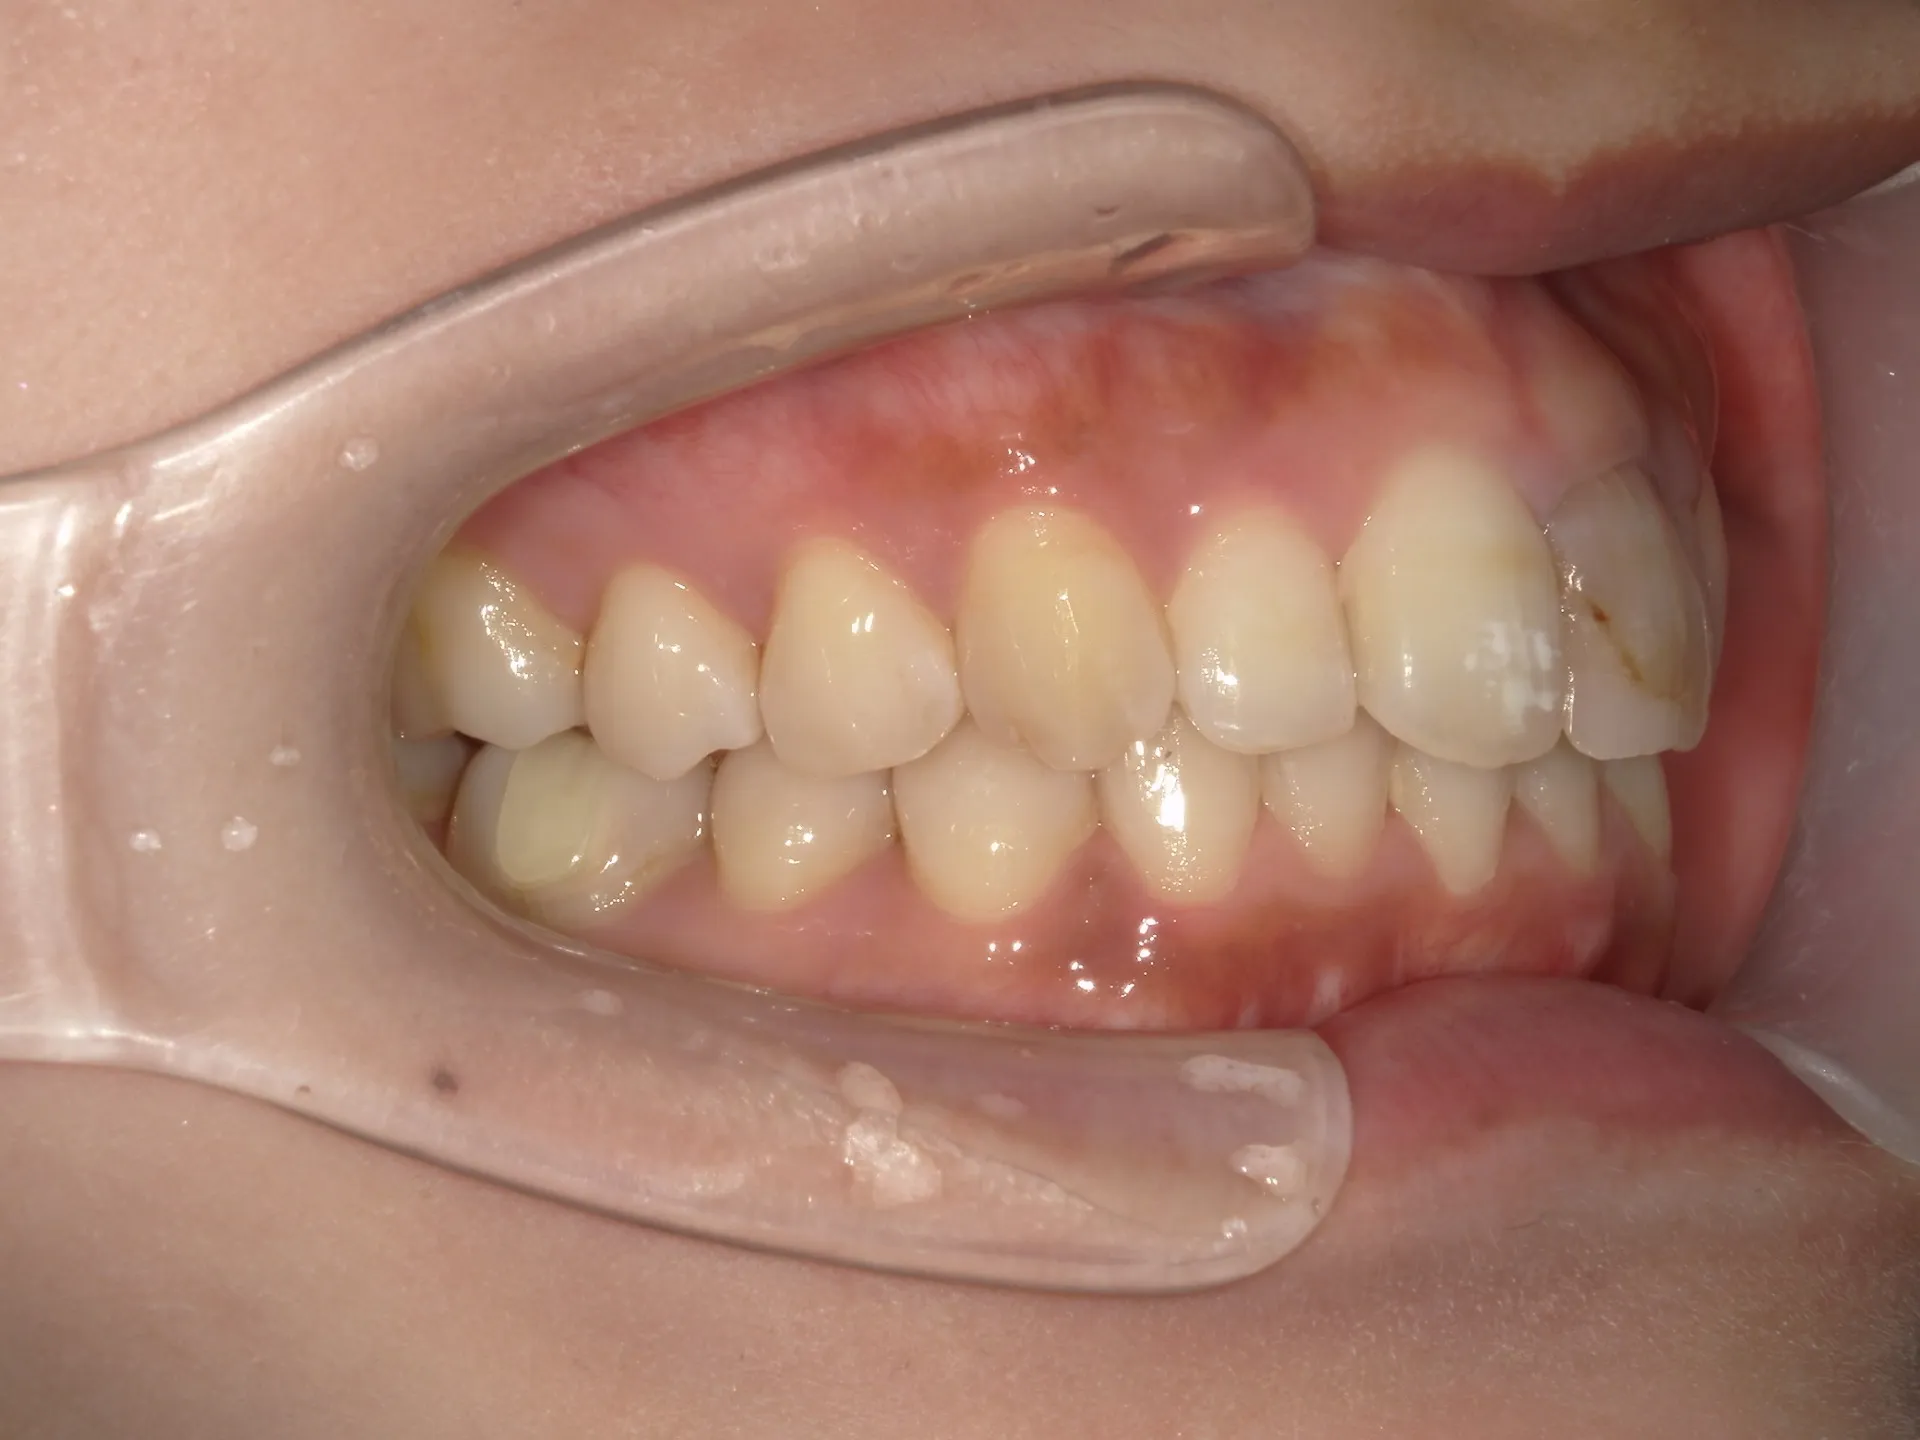

大きく飛び出してしまった前歯の矯正と変色の治療を希望された症例をご紹介いたします。